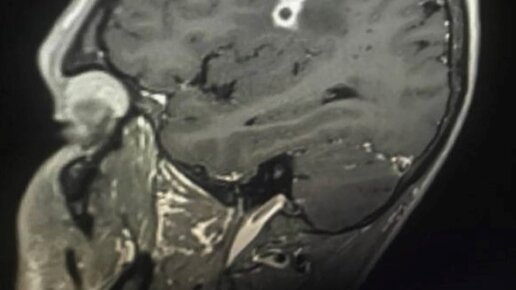

Тайсон Боттенус не придал значения тому, что упал с велосипеда на отдыхе в Коста-Рике. Он быстро поднялся, промыл раны и поехал дальше. Но когда Тайсон вернулся домой, начался ад. Сначала появились головные боли, потом парализовало лицо. Боль становилась хуже, Тайсон бегал по дому, не зная, как её утихомирить. Доступные обезболивающие, холодный или горячий душ, полная неподвижность или, наоборот, прогулки — все это, как казалось, только раззадоривает боль. Врачи проверили Тайсона на рак, паразитов, нейросифилис, болезнь Лайма и так далее...